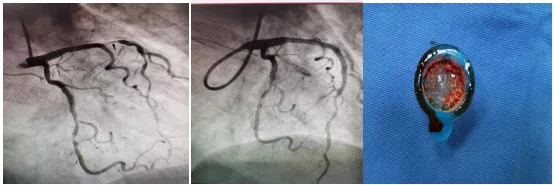

術中發現患者左冠狀動脈前降支近段95%瀰漫性狹窄,可見血栓影,中段80%節段性狹窄,遠端80%節段性狹窄,考慮為急性左冠脈前降支近段病變為罪犯病變,王健副主任立刻提出:運用血栓抽吸裝置對該部位進行血栓抽吸。隨後,抽吸出大量紅白色血栓,併為患者進行藥物球囊擴張。

術後患者恢復良好,繼續規範藥物治療,實現了急性心肌梗死患者“有介入、無植入”的最好結果。